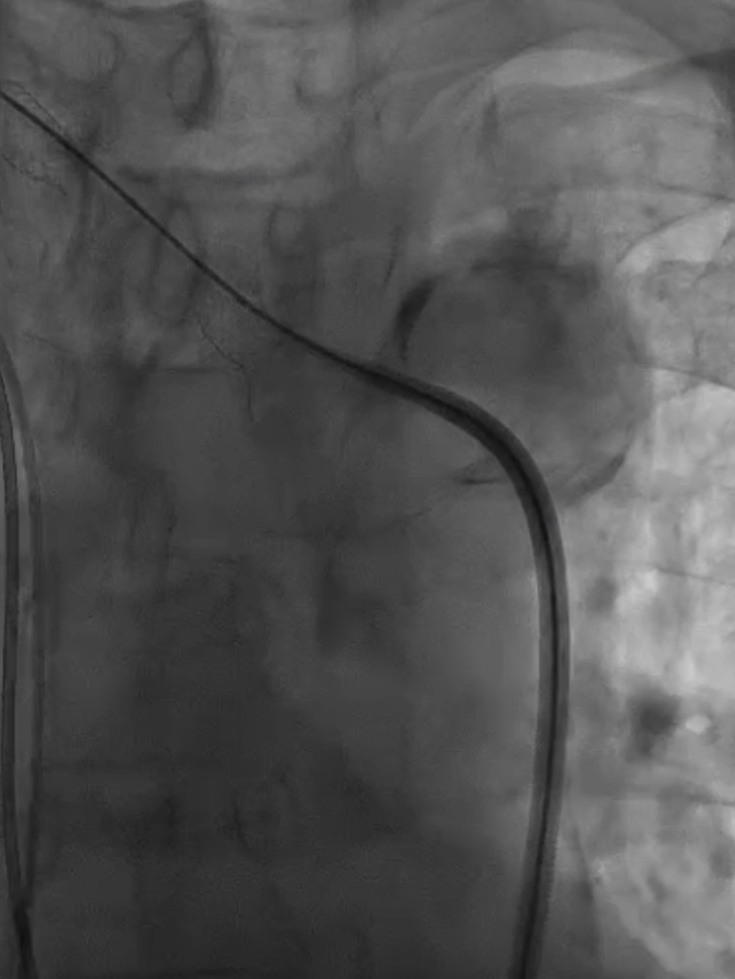

支架置入:通过“球囊带鞘”技术跟进长鞘至支架远端,采用同轴双导丝技术送入VBX8×29mm球扩覆膜支架,多角度造影定位后释放。

撤球囊时更进长鞘

至支架远端

同轴双导丝技术送入

VBX 8*29mm球扩覆膜

支架反复造影定位

释放支架

收尾操作:再次以球囊带鞘方式跟进长鞘至支架远端,回收保护伞;最终造影显示支架内血流通畅,右锁骨下动脉、右颈动脉、椎动脉显影良好,椎动脉血流速度较术前明显改善。

长鞘上行困难

回收保护伞

再次球囊带鞘

更进至支架远端

造影支架内通畅

右锁骨下动脉 右侧颈动脉

血流通畅椎动脉显影好